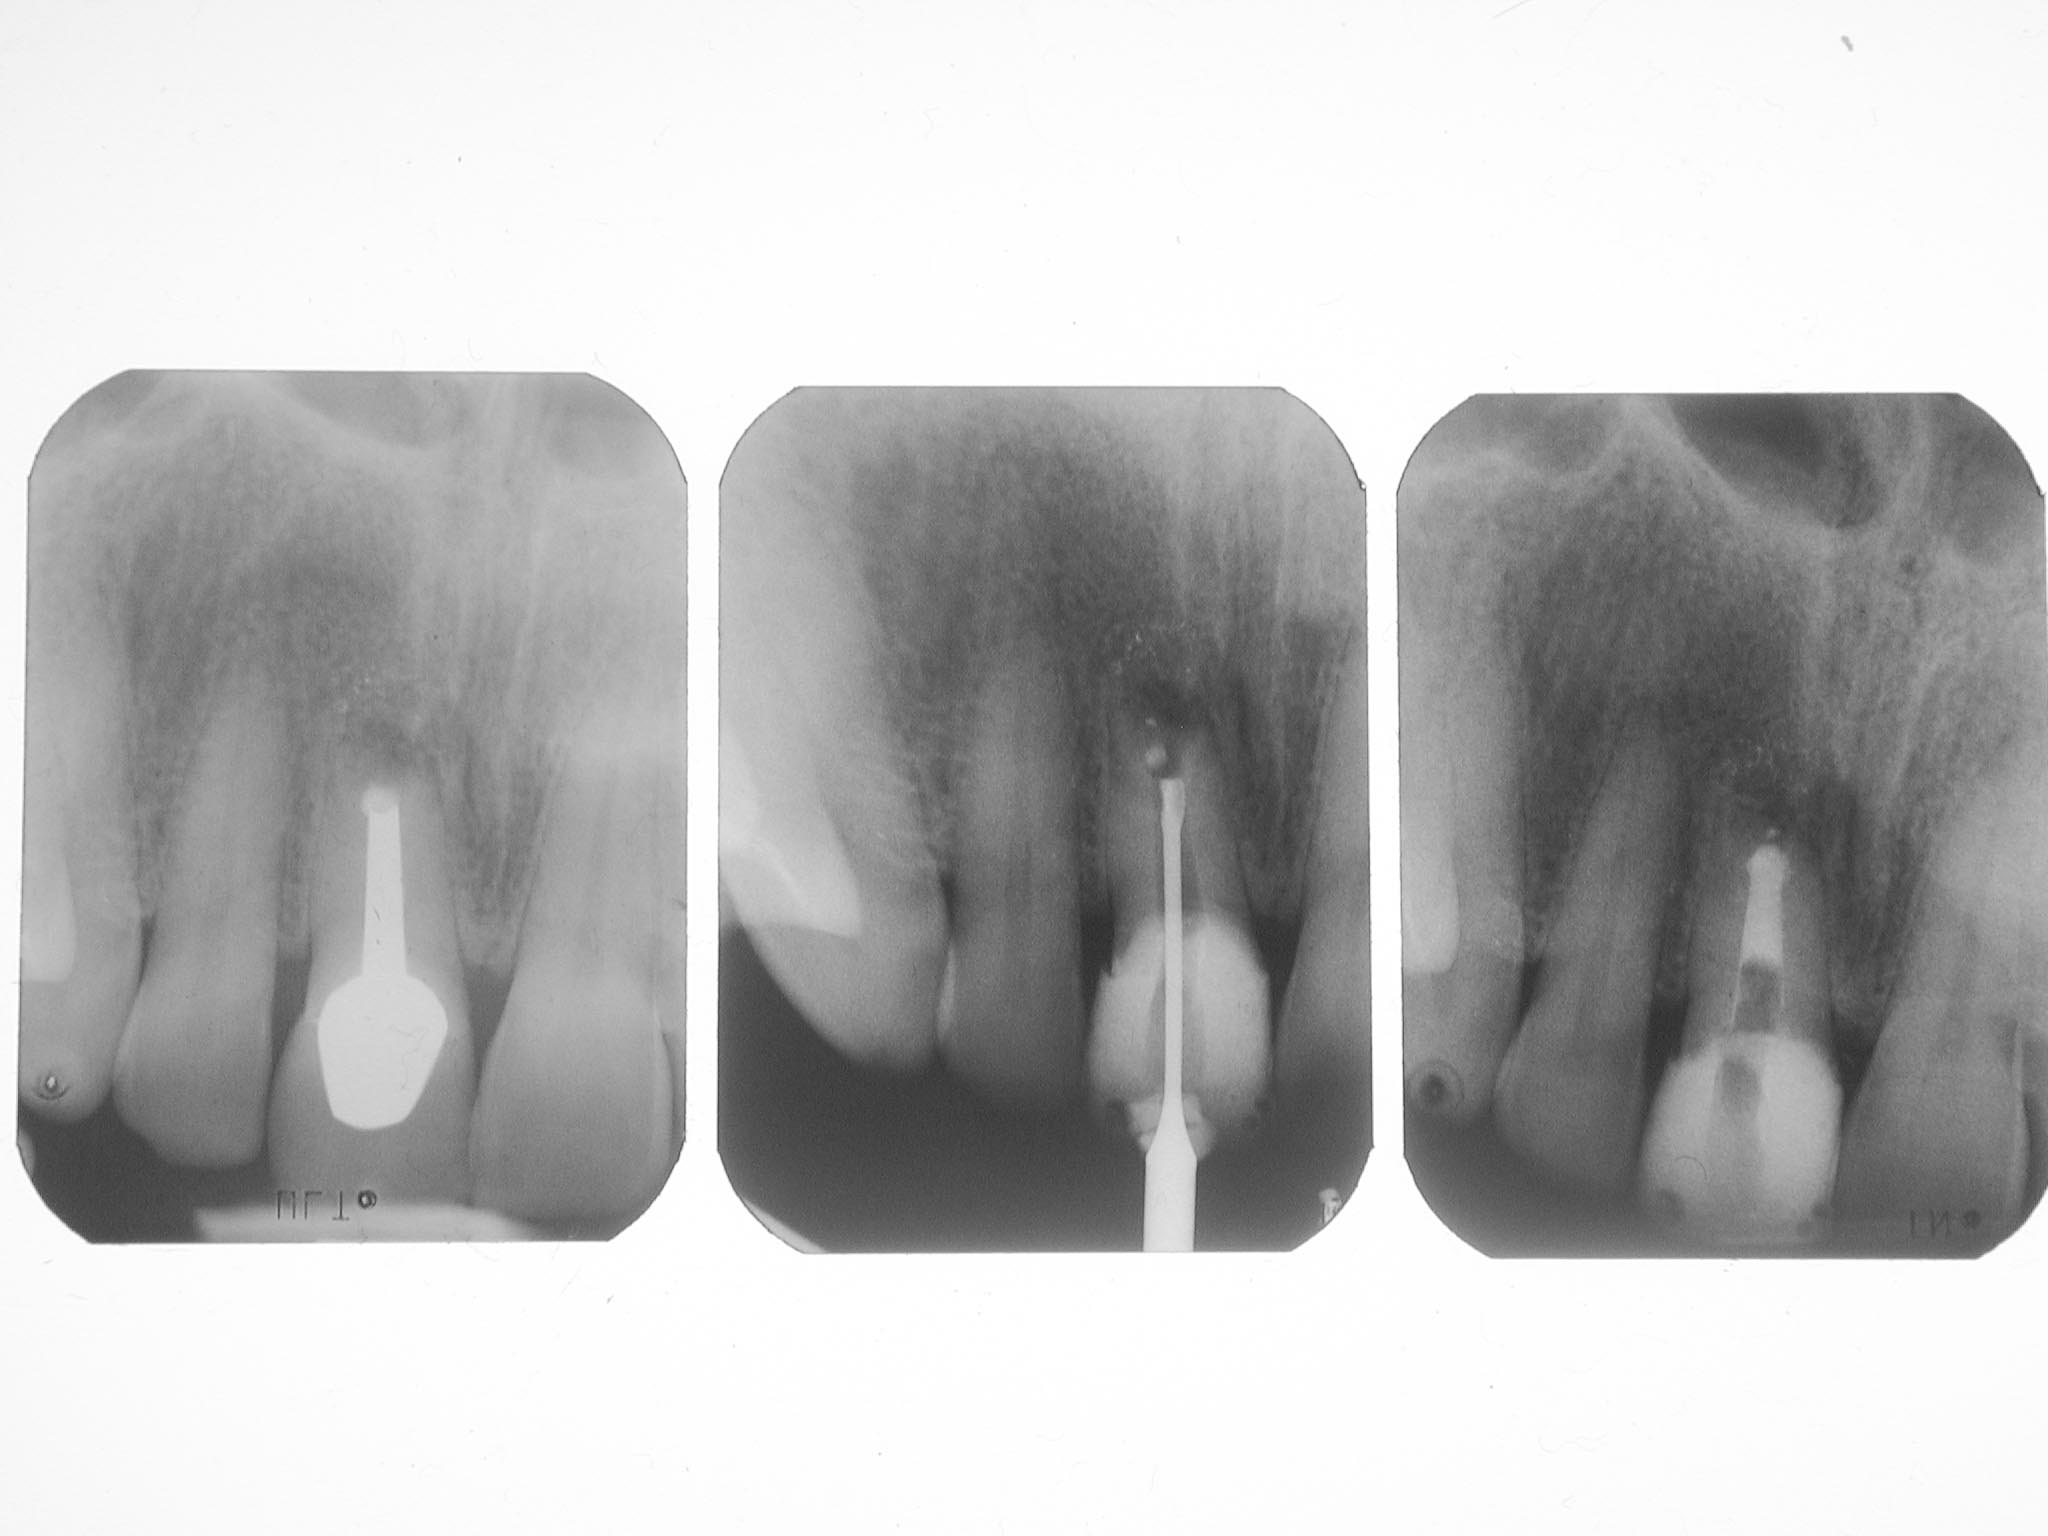

BB-1-8

(Miss)Erfolg des Tages